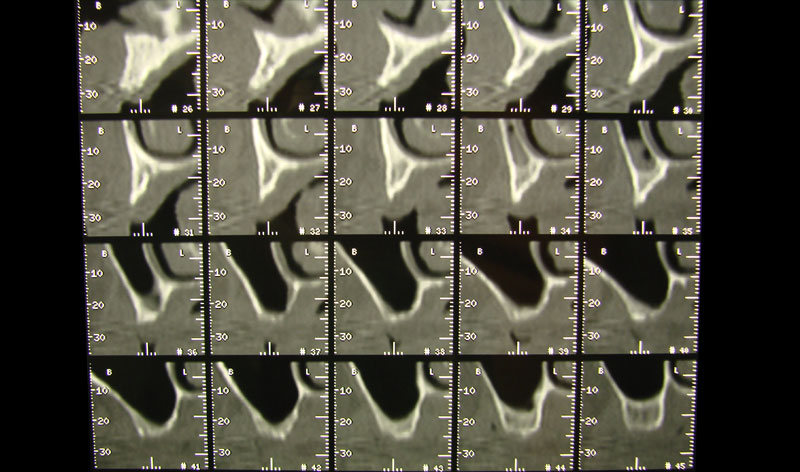

Existen muchas situaciones donde la pérdida y la atrofia ósea son tan graves que nos obligan a recurrir a la cresta iliaca del paciente, para conseguir el volumen óseo necesario para la correcta reconstrucción del maxilar. Así, la colocación de implantes será posible a los 3 meses.